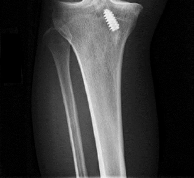

A 40-year-old skier sustains a highly comminuted Schatzker Type VI tibial plateau fracture.

Over the next few hours, he develops tense swelling of the lower leg, paresthesias in the first web space, and pain out of proportion to the injury with passive toe extension. If compartment pressures are measured to confirm acute compartment syndrome, which of the following provides the most reliable threshold for diagnosing the condition?